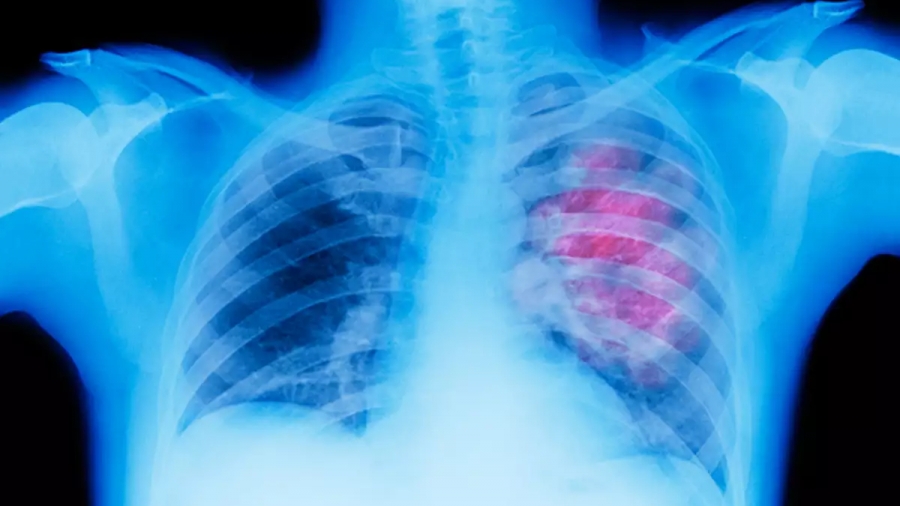

Στερεοτακτική Ακτινοθεραπεία Πνεύμονα: Ριζική λύση χωρίς χειρουργείο

ΤΣΑΜΑΣΙΩΤΗ.jpgΗ στερεοτακτική ακτινοθεραπεία είναι μια σχετικά νεότερη τεχνική θεραπείας που ήρθε να αλλάξει τα δεδομένα, επιτρέποντας τη χορήγηση μεγάλων θεραπευτικών δόσεων με υψηλή ακρίβεια και ασφάλεια.

Η τεχνική αυτή βρίσκει πολλές εφαρμογές σε όγκους (καλοήθεις και κακοήθεις) σε διάφορα σημεία του σώματος, με μια από τις πιο σημαντικές να αποτελεί η ακτινοβόληση του μη μικροκυτταρικού καρκίνου του πνεύμονα αρχικών σταδίων. Απευθύνεται λοιπόν σε ασθενείς με μικρούς όγκους (συνήθως μέχρι 5 εκατοστά) και χωρίς λεμφαδένες. Αποτελεί εξαιρετική επιλογή για ασθενείς που δεν μπορούν να υποβληθούν σε θεραπευτικό χειρουργείο για ιατρικούς λόγους (π.χ. προχωρημένη ηλικία, κακή αναπνευστική λειτουργία) ή που δεν επιθυμούν να υποβληθούν σε χειρουργική επέμβαση. Παρά το γεγονός ότι το χειρουργείο αποτελεί την πρώτη επιλογή, υπάρχουν μελέτες που δείχνουν ότι η στερεοτακτική ακτινοθεραπεία – σε σωστά επιλεγμένους ασθενείς – προσφέρει τα ίδια ποσοστά επιβίωσης.